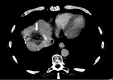

Figure 1

Figure 1. Axial CT abdomen in the portovenous phase in liver window demonstrating the segment 4a tumor (white arrow).